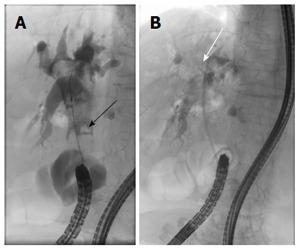

Here, we report our experience with a case of severe biliary bleeding due to a hepatic arterial pseudoaneurysm that had developed 1 year after endoscopic biliary plastic stent insertion. The patient, a 78-year-old woman, presented with hematemesis and obstructive jaundice. Ruptured hepatic arterial pseudoaneurysm was diagnosed, which was suspected to have been caused by long-term placement of an endoscopic retrograde biliary drainage (ERBD) stent. This episode of biliary bleeding was successfully treated by transarterial embolization (TAE). Pseudoaneurysm leading to hemobilia is a rare but potentially fatal complication in patients with long-term placement of ERBD. TAE is a minimally invasive procedure that offers effective treatment for biliary bleeding.

在此,我们报告一例因肝动脉假性动脉瘤导致严重胆道出血的病例,该假性动脉瘤在内镜下胆道塑料支架置入术后1年形成。患者为一名78岁女性,表现为呕血和梗阻性黄疸。诊断为破裂的肝动脉假性动脉瘤,怀疑是由内镜逆行胆道引流(ERBD)支架长期放置引起的。通过经动脉栓塞术(TAE)成功治疗了这例胆道出血。导致胆道出血的假性动脉瘤在长期放置ERBD的患者中是一种罕见但可能致命的并发症。TAE是一种微创手术,可为胆道出血提供有效的治疗。